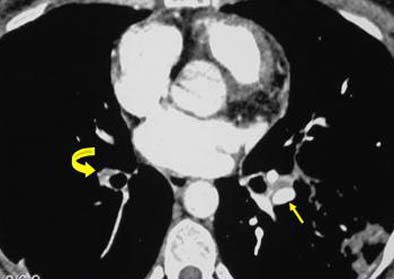

Retraction: Evidence of arterial retraction is the most telling sign that the PE findings are chronic rather than acute. Retraction can be ascertained by comparing the diameter of the suspect arteries with the contralateral vessels. Retraction is the most significant finding in chronic PE, and the diagnosis cannot be contemplated in its absence, she said.

![]() |

| Retraction of embolic material. |

Calcification: Calcification of emboli is commonly seen in chronic PE. However, it can occur in a number of disorders, she said.

| Calcification of embolic material. Maximum intensity projections (MIPS, above right, W: 1900 HU, C: 370 HU) are often helpful in distinguishing hard-to-find calcifications. |